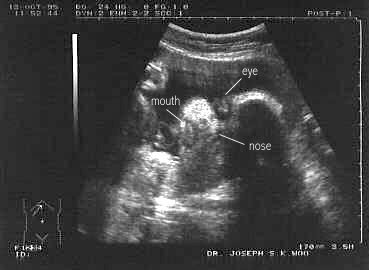

En las embarazadas permite asegurar entre otras cosas que existe la gestación, que el producto se encuentra vivo, descarta malformaciones fetales y sirve para controlar el crecimiento del bebé a través de curvas de crecimiento.

Entre sus más grandes avances se encuentra el control del crecimiento y desarrollo del bebé en la mujer embarazada.